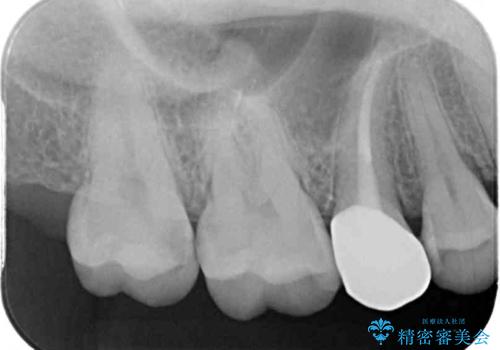

- 近々海外へ転居するとのことで、事前に処置をしておくべきむし歯がないか、気にして来院された患者様です。

レントゲン写真などから、速やかに処置を行うべき歯が2歯あったため、それぞれセラミックインレーとPGAインレー(ゴールドインレー)にて修復治療を行うこととしました。